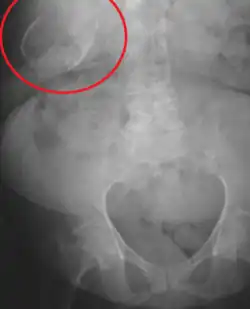

Porcelain gallbladder

Porcelain gallbladder on X-ray | |

Porcelain gallbladder is a calcification of the gallbladder believed to be brought on by excessive gallstones, although the exact cause is not clear. As with gallstone disease in general, this condition occurs mostly in overweight female patients of middle age. It is a morphological variant of chronic cholecystitis. Inflammatory scarring of the wall, combined with dystrophic calcification within the wall transforms the gallbladder into a porcelain-like vessel. Removal of the gallbladder (cholecystectomy) is the recommended treatment.

Abdominal radiography (X-ray), abdominal ultrasound or CT scan.